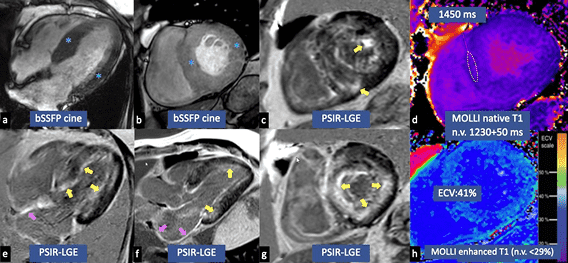

ÉCHOGRAPHIE4

- Phénotype hypertrophique avec manifestations infiltrantes

- Remplissage du VG restrictif et épaississement de la paroi du VD

- Faible vélocité de l’onde e' à l’anneau mitral septal ou latéral

- Réduction de la déformation longitudinale globale